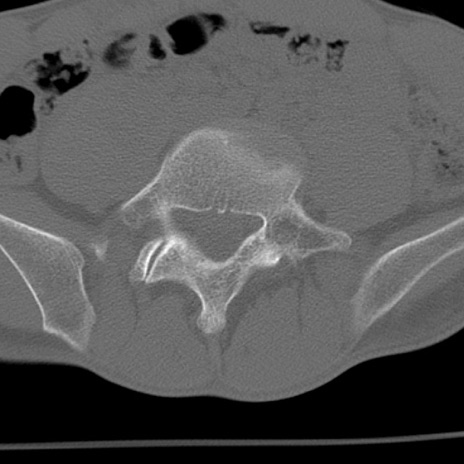

症例3 腰椎CT(横断像)

腰椎CT